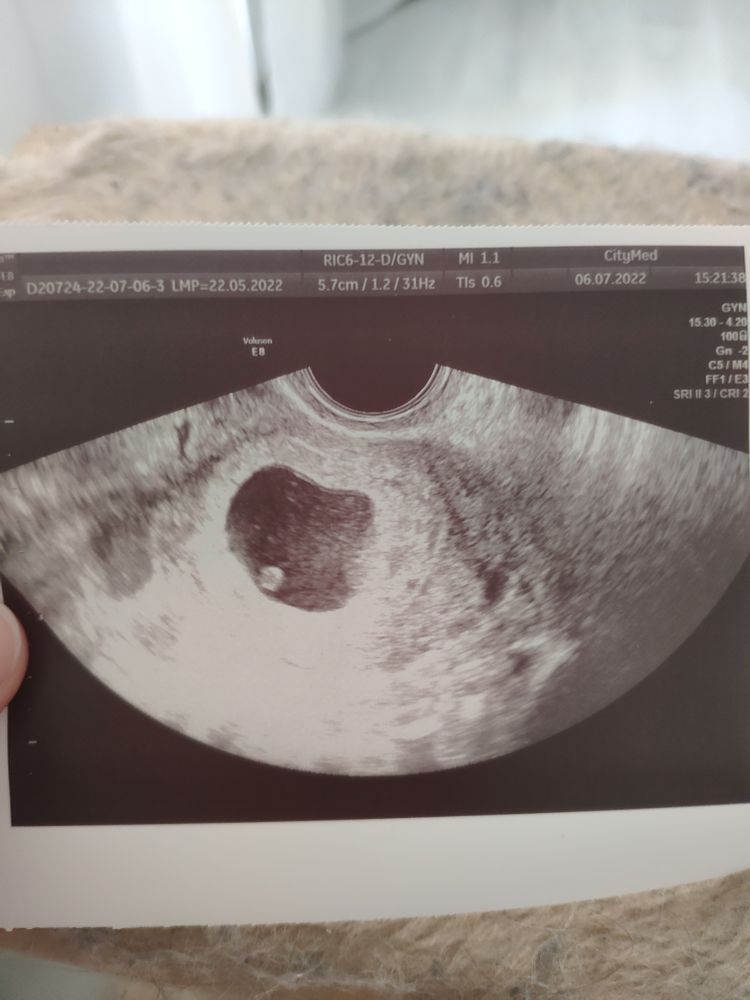

Привет))у меня сегодня по УЗИ 6+1)) тоже нет токсикоза и вообще особых симптомов)грудь набухла чуток)

06.07.2022

Катя, ух ты! Класс!! Эмбриончик такой уже заметный!!)) даже вглядываться не надо)

Кама, нам его даже показали,показали как пульсирует сердечко)))такие милые два пикселя)ктр 4мм) сердцебиение просто плюс поставили) сказали только через пару недель на учёт вставать)